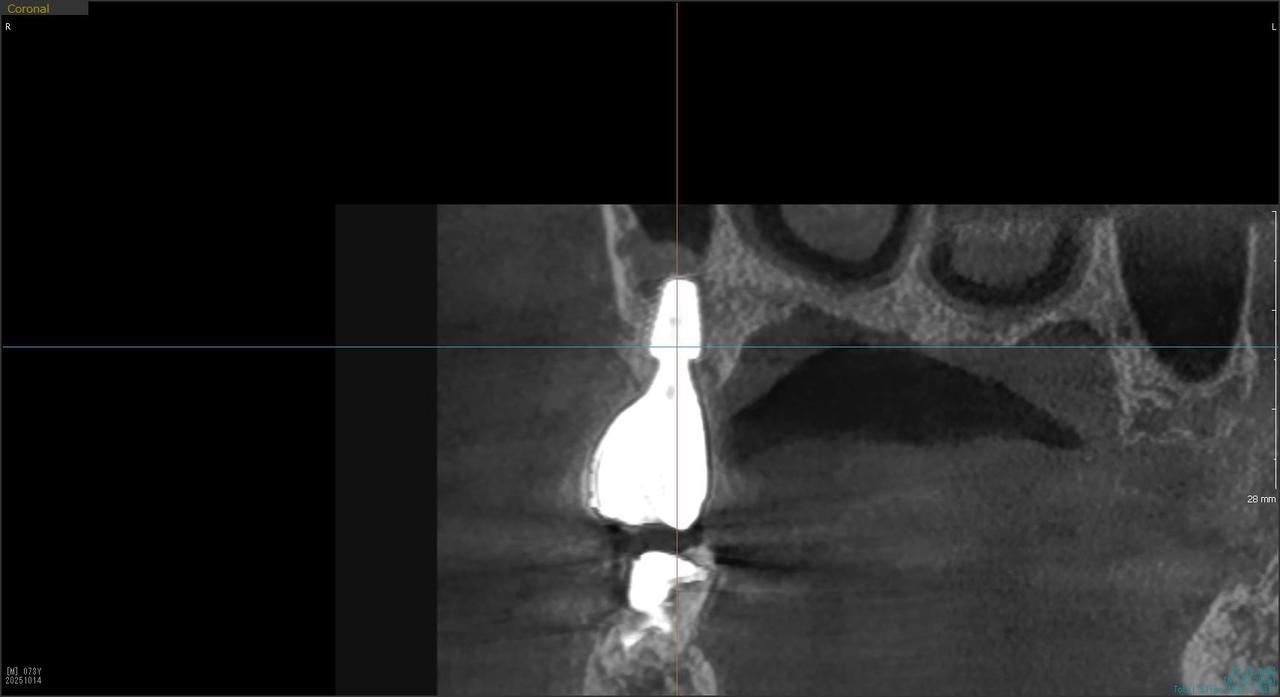

2.右上6番の上顎既存骨2mmのグラフトレスサイナスリフト(骨補填剤を使わない上顎洞挙上術)のケース

Before

枚方市のインプラントの症例

K・Y 様 女性 50代

症状としては、右上6番の歯が歯周病のため、自然に抜けてしまった。

治療法としては、歯周病により、右側6番の上顎骨が吸収して、2mm程度の骨しか残っていなかったため、サイナスリフトが必要であった。通常のサイナスリフトだと時間(時間的には1年から1年半程度かかると考えます。)と費用がかかり、患者様への時間的、肉体的、金銭的負担が大きくなることを考慮して、今回は、インプラントの種類としては、エクストラワイドショートインプラント、術式としては、デンサーバーを使用したグラフトレスサイナスリフトを選択しました。最終補綴物はジルコニアで仕上げています。

結果としては、高度に吸収した上顎骨に対するインプラント治療であったが、グラフトレスサイナスリフトを行うことで、短時間(2か月半程度)で治療を終えることができた。また、サイナスリフトによくある術後合併症である上顎洞炎を起こすことなく、患者様への肉体的な負担を抑えた治療を行うことができた。また、上顎右側6番にインプラント治療できたことにより、咬合が安定するとともに、歯周病にり患している上顎の他の歯に対する負担を少なくすることができた。

治療の期間・回数:約2か月半、6回

治療の価格:363,000円(税込)

治療費の内訳:インプラント基本料(フィックスチャー及び手術費用、投薬費用、レントゲン費用、インプラント上部費用(アバットメントおよびジルコニアクラウンの費用用)330000円(税込み)オプション費用グラフトレスサイナスリフト費用 33000円(税込み)